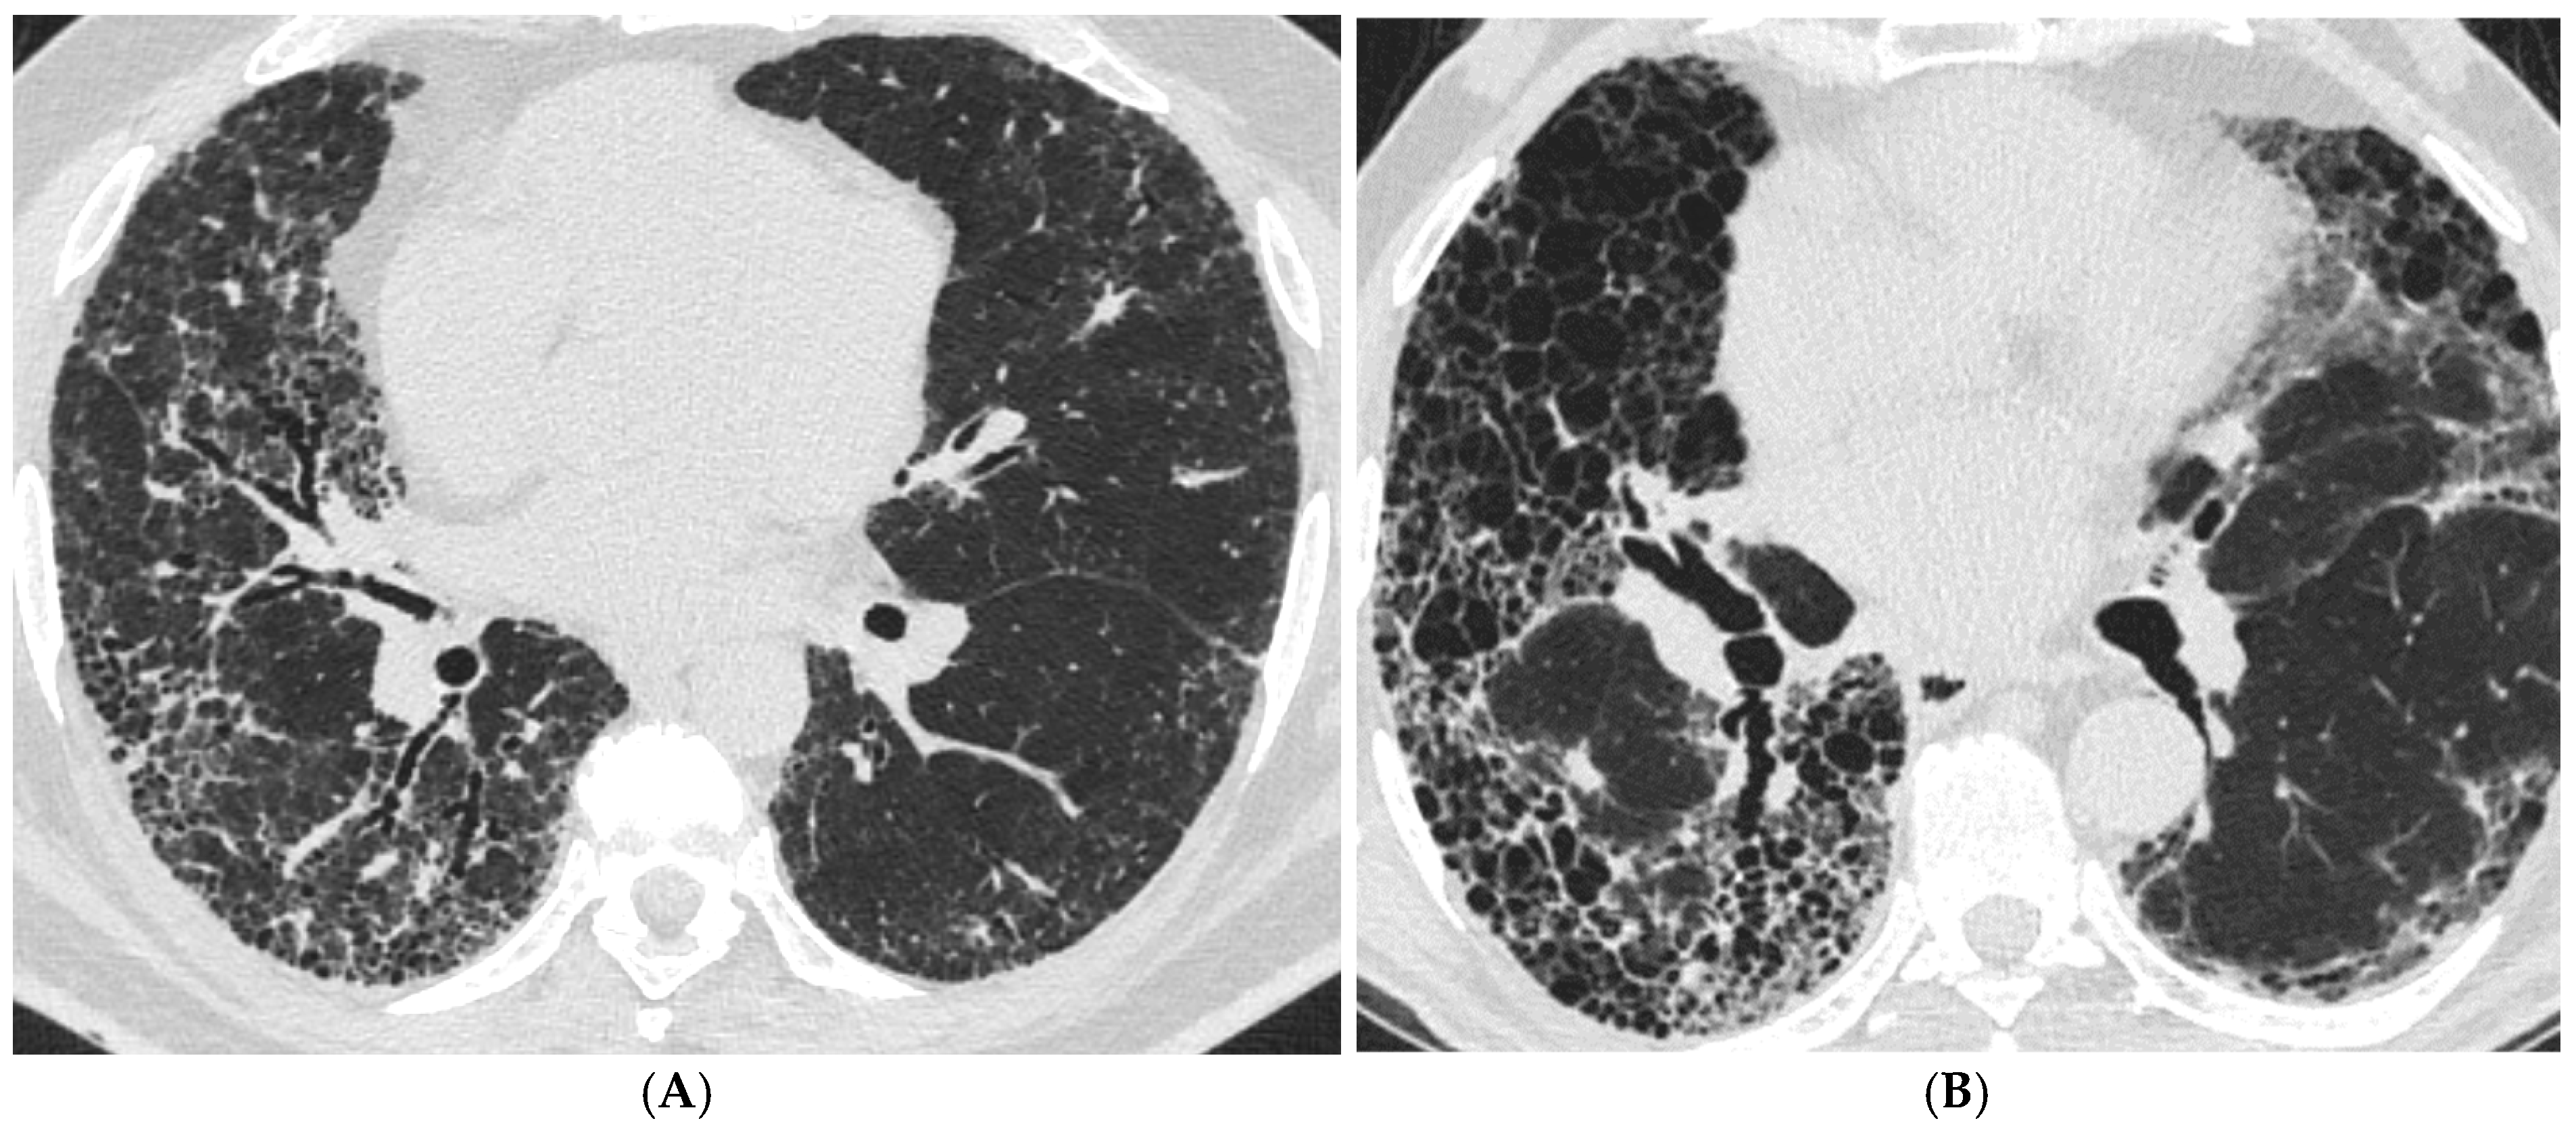

The Role of High-Resolution Lung Computed Tomography to Distinguish Between Fibrosing Hypersensitivity Pneumonitis and Usual Interstitial Pneumonia

3.2. HRCT Patterns in the Groups